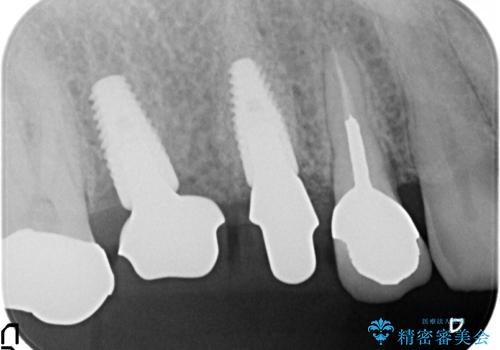

右上の567ブリッジを外したところ、右上5は歯根破折により保存不可能だったため、右上56部にインプラントを埋入し欠損補綴を行いました。

また右上5部に関しては抜歯時に歯槽堤保存術(抜歯窩に人工骨の填入を行う手術)を行い、骨の欠損を最小限に止めています。

ストローマン(インプラント)について

当院では主にストローマンという種類のインプラントを治療に用いています。

ストローマンは世界的にもNo1のシェアを誇り、骨との適合にも優れたインプラントです。

カスタムアバットメントについて

カスタムアバットメントは患者様それぞれの歯茎に合わせて製作されたオーダーメイドのアバットメントです。

既製のアバットメントに比べ適合がよく、高い清掃性を誇ります。